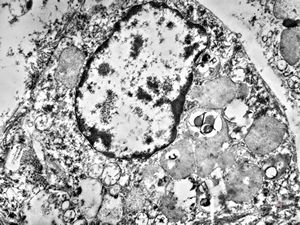

M,3y. | normal hepatocyte